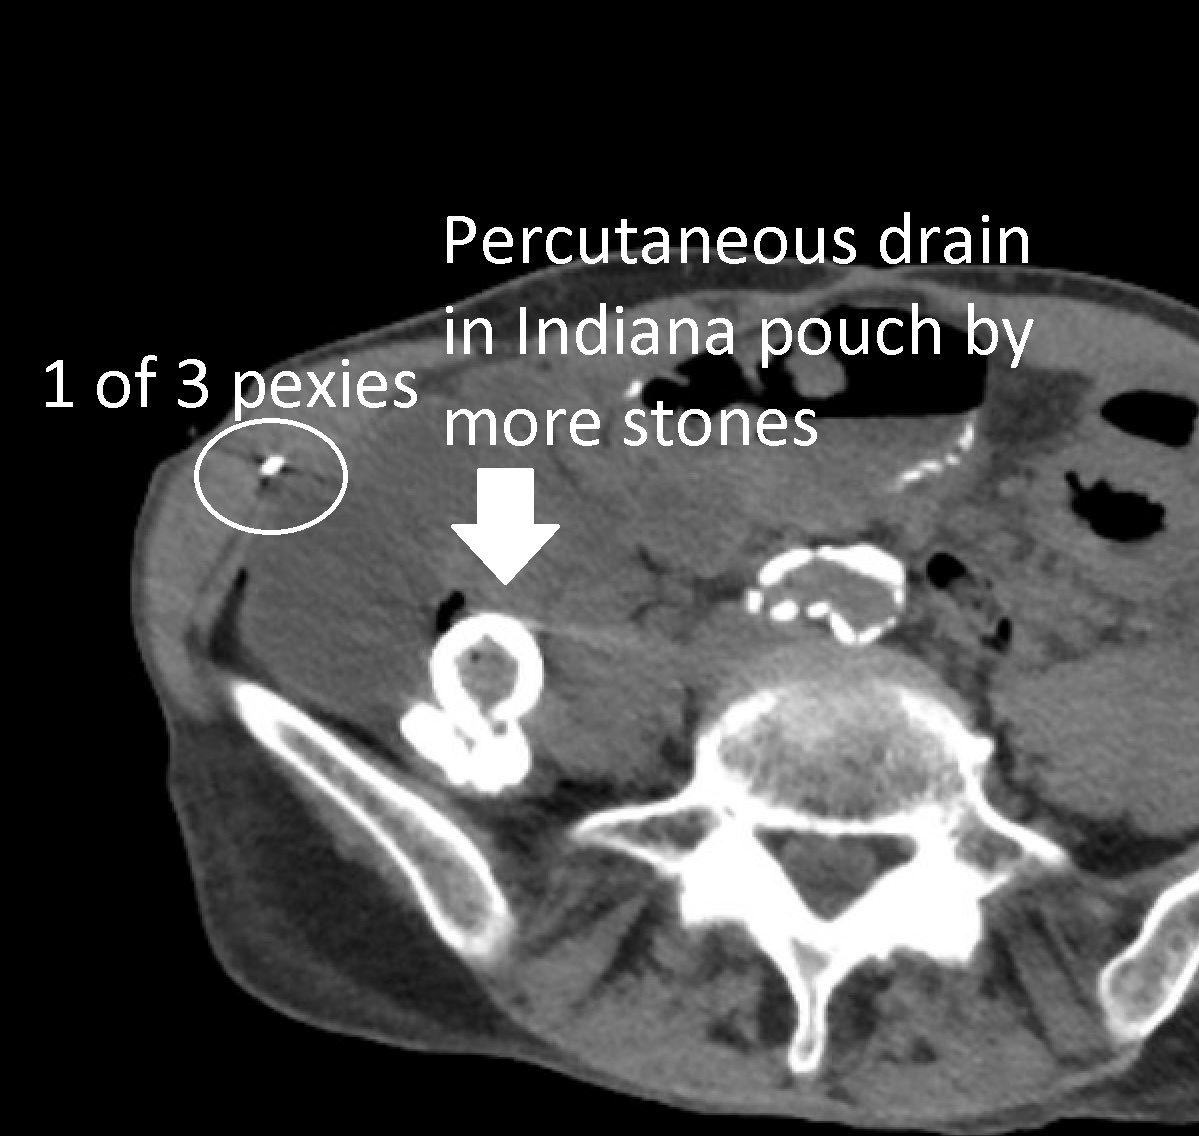

I love working with my colleagues @uabmedicine to come up with solutions for patients, like in this case. Interventional radiology (#IRad) placed a percutaneous drain into an Indiana pouch to facilitate percutaneous nephrolithotomy. The text message follow up is the best part!